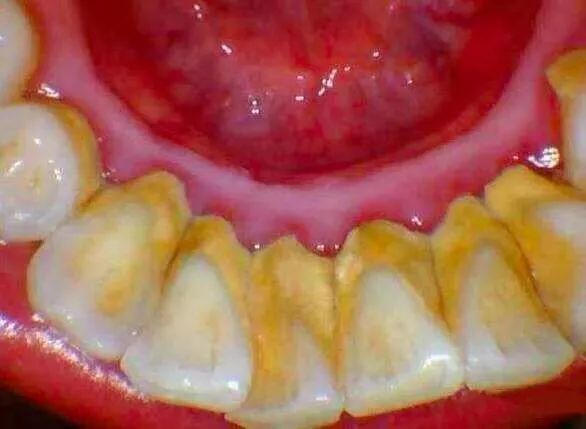

这是一个 30 多岁的小伙子,只是因为「牙齿松动」来就诊。但等待他的,却是晚期牙周炎患者的最终归宿——全口牙松动,拔除。牙周炎患者被拔除的牙齿↓↓↓

换句话说,他看起来一颗牙也不缺,但其实一颗牙也没有了——这就是晚期牙周炎患者面对的「无牙窘境」。然而,对口腔大夫来说,这样「全口牙齿拔除」的骇人病例,却已经司空见惯。